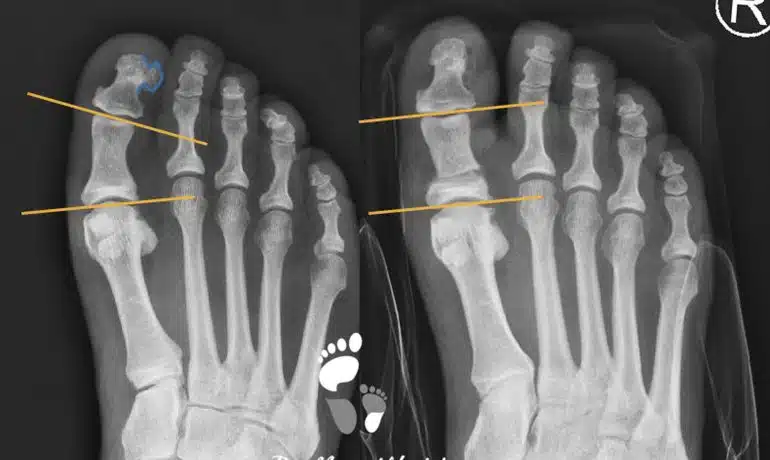

Distale Metaphysäre Metatarsale Osteotomie (DMMO)

Diese Operationstechnik wird bei Metatarsalgie angewendet. Die Hauptindikationen sind eine Überlänge der Metatarsalia 2-4 (griechische Fußform) und eine Transfermetatarsalgie nach Hallux valgus-Korrektur.Im Prinzip werden durch...